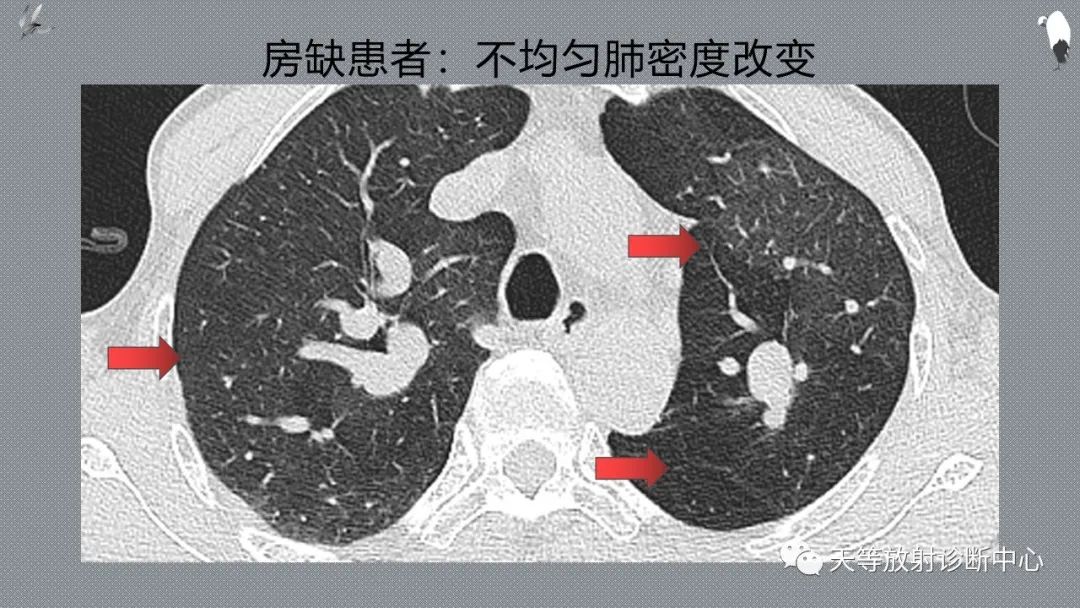

以下病人容易出现马赛克伪影,HRCT注意区别于肺部磨玻璃影,改变体位扫描或短期内复查有助于鉴别

老年患者

呼吸不配合的病人

慢性肺部疾病,慢性支气管炎、心脏病的患者、肺气肿病人

多种系统性疾病患者

神经系统疾病的患者